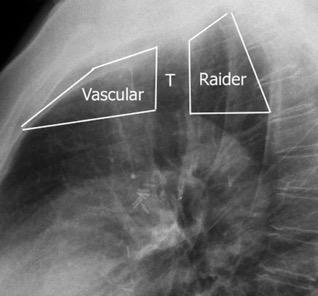

Raider L. The Retrotracheal Triangle. Chest. 1973./ Franquet T et al.

The Retrotracheal Space: Normal Anatomic and Pathologic Appearances. RadioGraphics. 2002

Aneurisma (aórtico, AS aberrante)

Normal

Divertículo de Zenker, Acalasia, Q. duplicación, Bocio, T. neurogénico, Hemangioma, Linfangioma, Hematoma Tuberculosis, Absceso